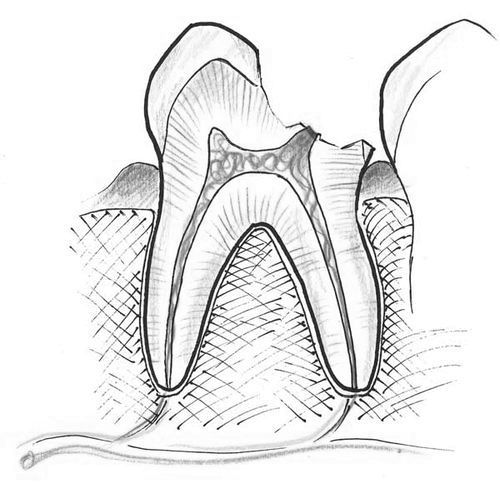

З огляду на те, що процес хвороби протікає під коронковой частиною зуба і захований в яснах, діагностувати його буває нелегко. Особливо, якщо пришийкова зона зубів покрита твердими утвореннями. Знімаючи камені і роблячи рентгенограму, лікар може виявити карієс, який вразив корінь.

- Проблеми з яснами. Багато хвороб ясен супроводжуються виникненням глибоких ясенних кишень, в яких накопичуються залишки їжі і розвиваються хвороботворні мікроби. На корені немає захисного емалевого шару, а значить, патогенні бактерії без зволікання починають його руйнувати.

- Збіг двох таких факторів, як - пришийковий карієс і оголений біля основи корінь.

- Установка коронки, яка одночасно опускає ясна і оголює кореневе підставу, роблячи його беззахисним до бактерій.

Проводячи лікування каріозної хвороби, важливо бути впевненим в тому, що вона «не повернеться». Як і звичайний карієс, кореневої тип потребує пломбування та попередньому очищенні від уражених ділянок. Уражені тканини січуться в повному обсязі, що перевіряється карієс-індикатором. Після цього лікар виконуємо пломбування.